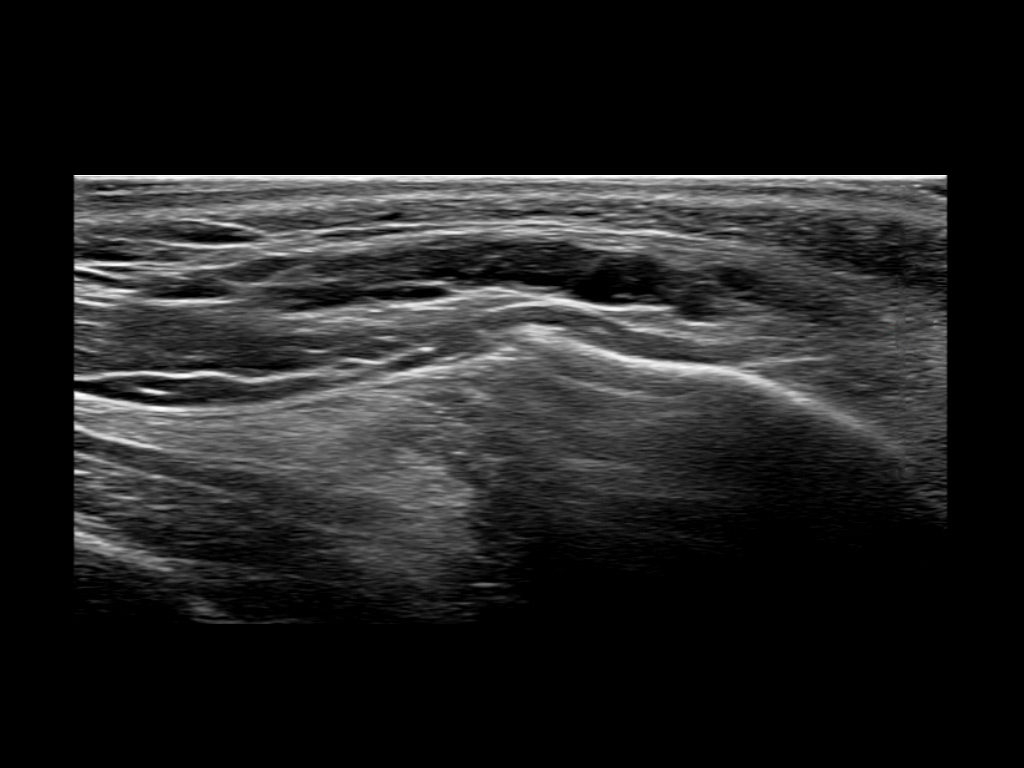

Filler behavior - Temple zygoma US

Study the first image to recognize the different layers. If you are sure about the layers, swipe to the second image to view the answer (if applicable).